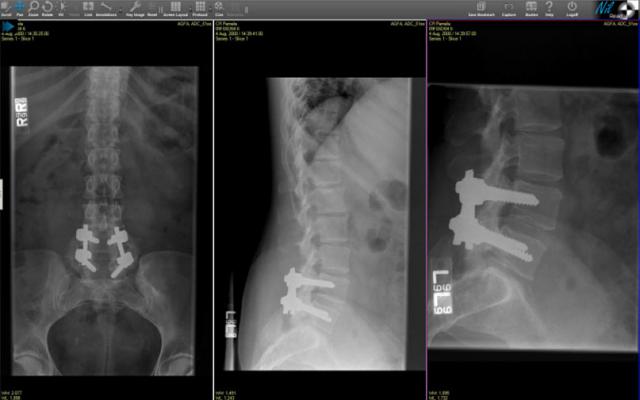

October 21, 2013 — Claron Technology announced U.S. Food and Drug Administration (FDA) clearance of NilRead zero-footprint viewer for the diagnostic interpretation of medical images. NilRead is the first universal, Web-based zero-footprint viewer supporting multi-monitor configurations.

A full-featured medical imaging viewer, NilRead enables diagnostic interpretation of medical images and related digital information on a variety of computers anytime, anywhere across the enterprise.  It supports diagnostic viewing of all cleared digital imaging and communications in medicine (DICOM) imaging modalities on single or multi-monitor configurations.  Running from a remote server, the viewer supports high-resolution, diagnostic-quality medical images and data formats with no software download and no compromise on performance.

The viewer also features customizable hanging protocols, prior-current comparison and extensive measurements.  Its advanced visualization features include thin/thick slabs, MIP, volume rendering and positron emission tomography (PET)/computed tomography (CT) fusion. It delivers the highest levels of security and leaves no information on the viewing hardware when the session is complete.